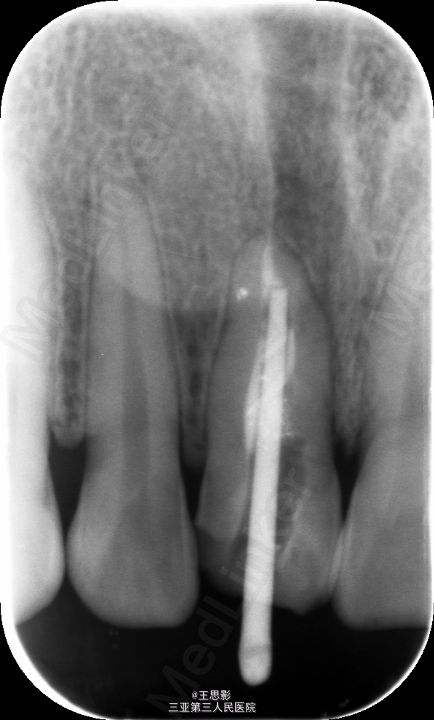

X线片显示,再治疗根充影像可,密度及长度已达要求